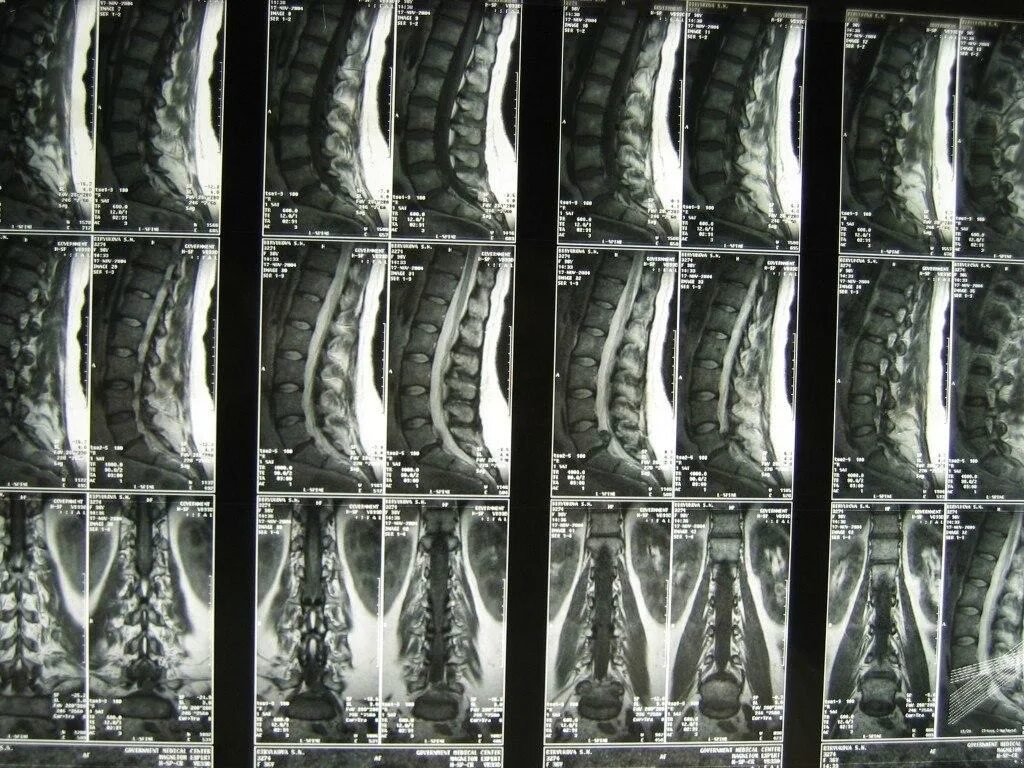

Мрт или кт позвоночника при болях